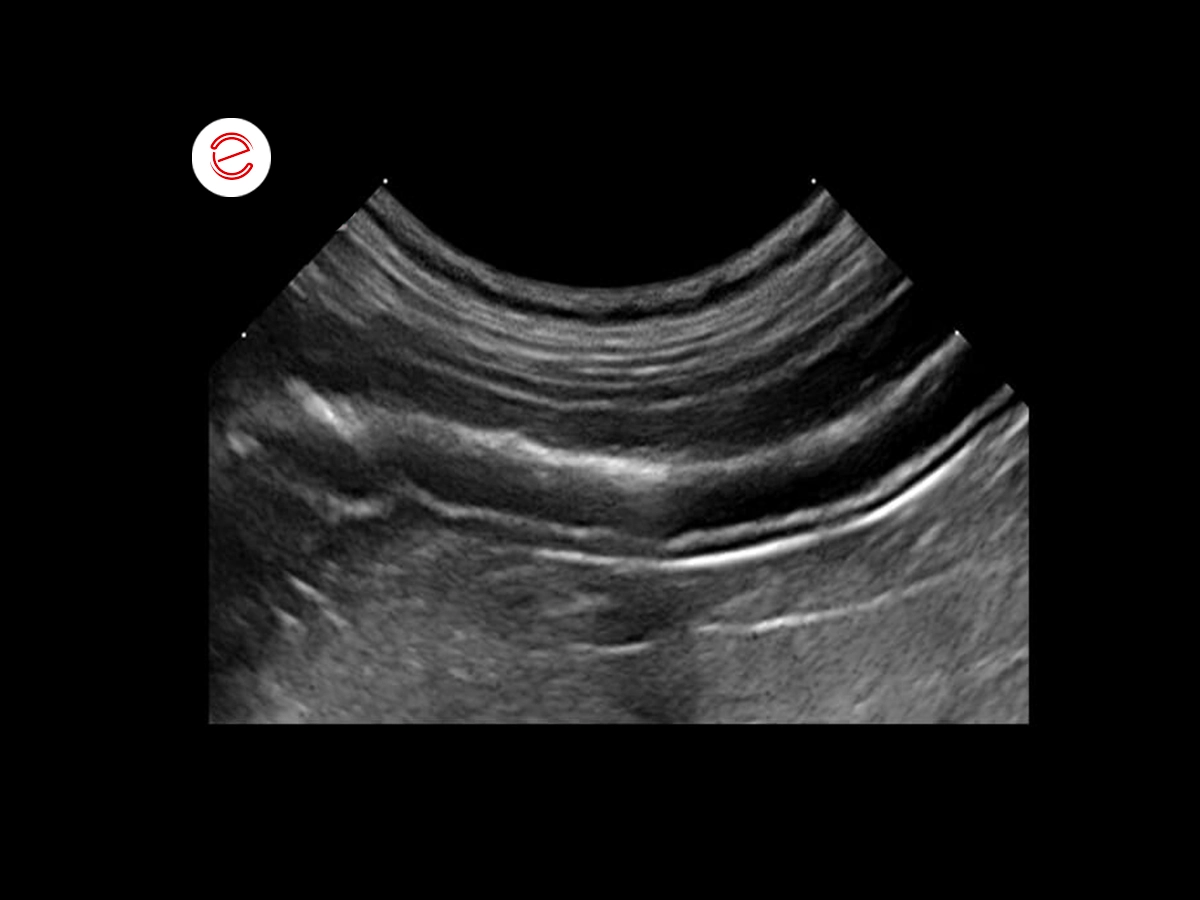

Ecografia del fegato

L'esame ecografico del fegato ha evidenziato un pattern ecogeno aumentato e non omogeneo.

È stata quindi eseguita una biopsia epatica.